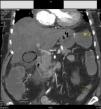

A las 8 h de la intervención, la paciente todavía con ventilación mecánica, comienza bruscamente con oliguria, hipotensión y taquicardia. En la analítica destaca un aumento de las cifras de lactato de hasta 9,3mg/dl, con Hb de 8,3g/dl (salió del quirófano con 11g/dl) sin débito hemático por los drenajes. Se realiza una endoscopia digestiva alta para descartar sangrado digestivo, apreciando mucosa gástrica de aspecto isquémico. En analítica de control destaca: GOT 4.418, GPT 3.195, actividad de protrombina del 33%, CPK 9013. La TC de urgencia informó de hígado con áreas parcheadas hipodensas, con arteria hepática y vena porta permeables, colecistitis enfisematosa alitiásica y trombosis de arteria renal izquierda desde su salida de la aorta (fig. 1).

La clínica que presentan estos pacientes inicialmente es similar a la colecistitis aguda simple, pudiendo evolucionar excepcionalmente de manera fulminante. En la TC abdominal con contraste podemos observar las imágenes demostrativas de gas perivesicular (fig. 1). Esta entidad se considera una urgencia quirúrgica y su tratamiento de elección es la colecistectomía inmediata, asociando amplia cobertura antibiótica. A pesar de un tratamiento adecuado la mortalidad, en estos pacientes es aproximadamente de un 15%.